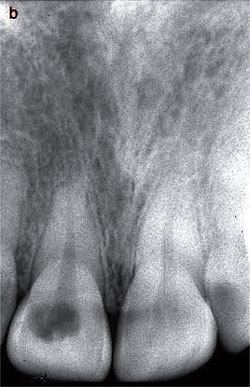

film ของฟันหลัง ที่เจอ Invasive cervical resorption Class 2

ในคลินิก มองไม่เห็นความผิดปกติใดๆ (ไม่มี discoloration)